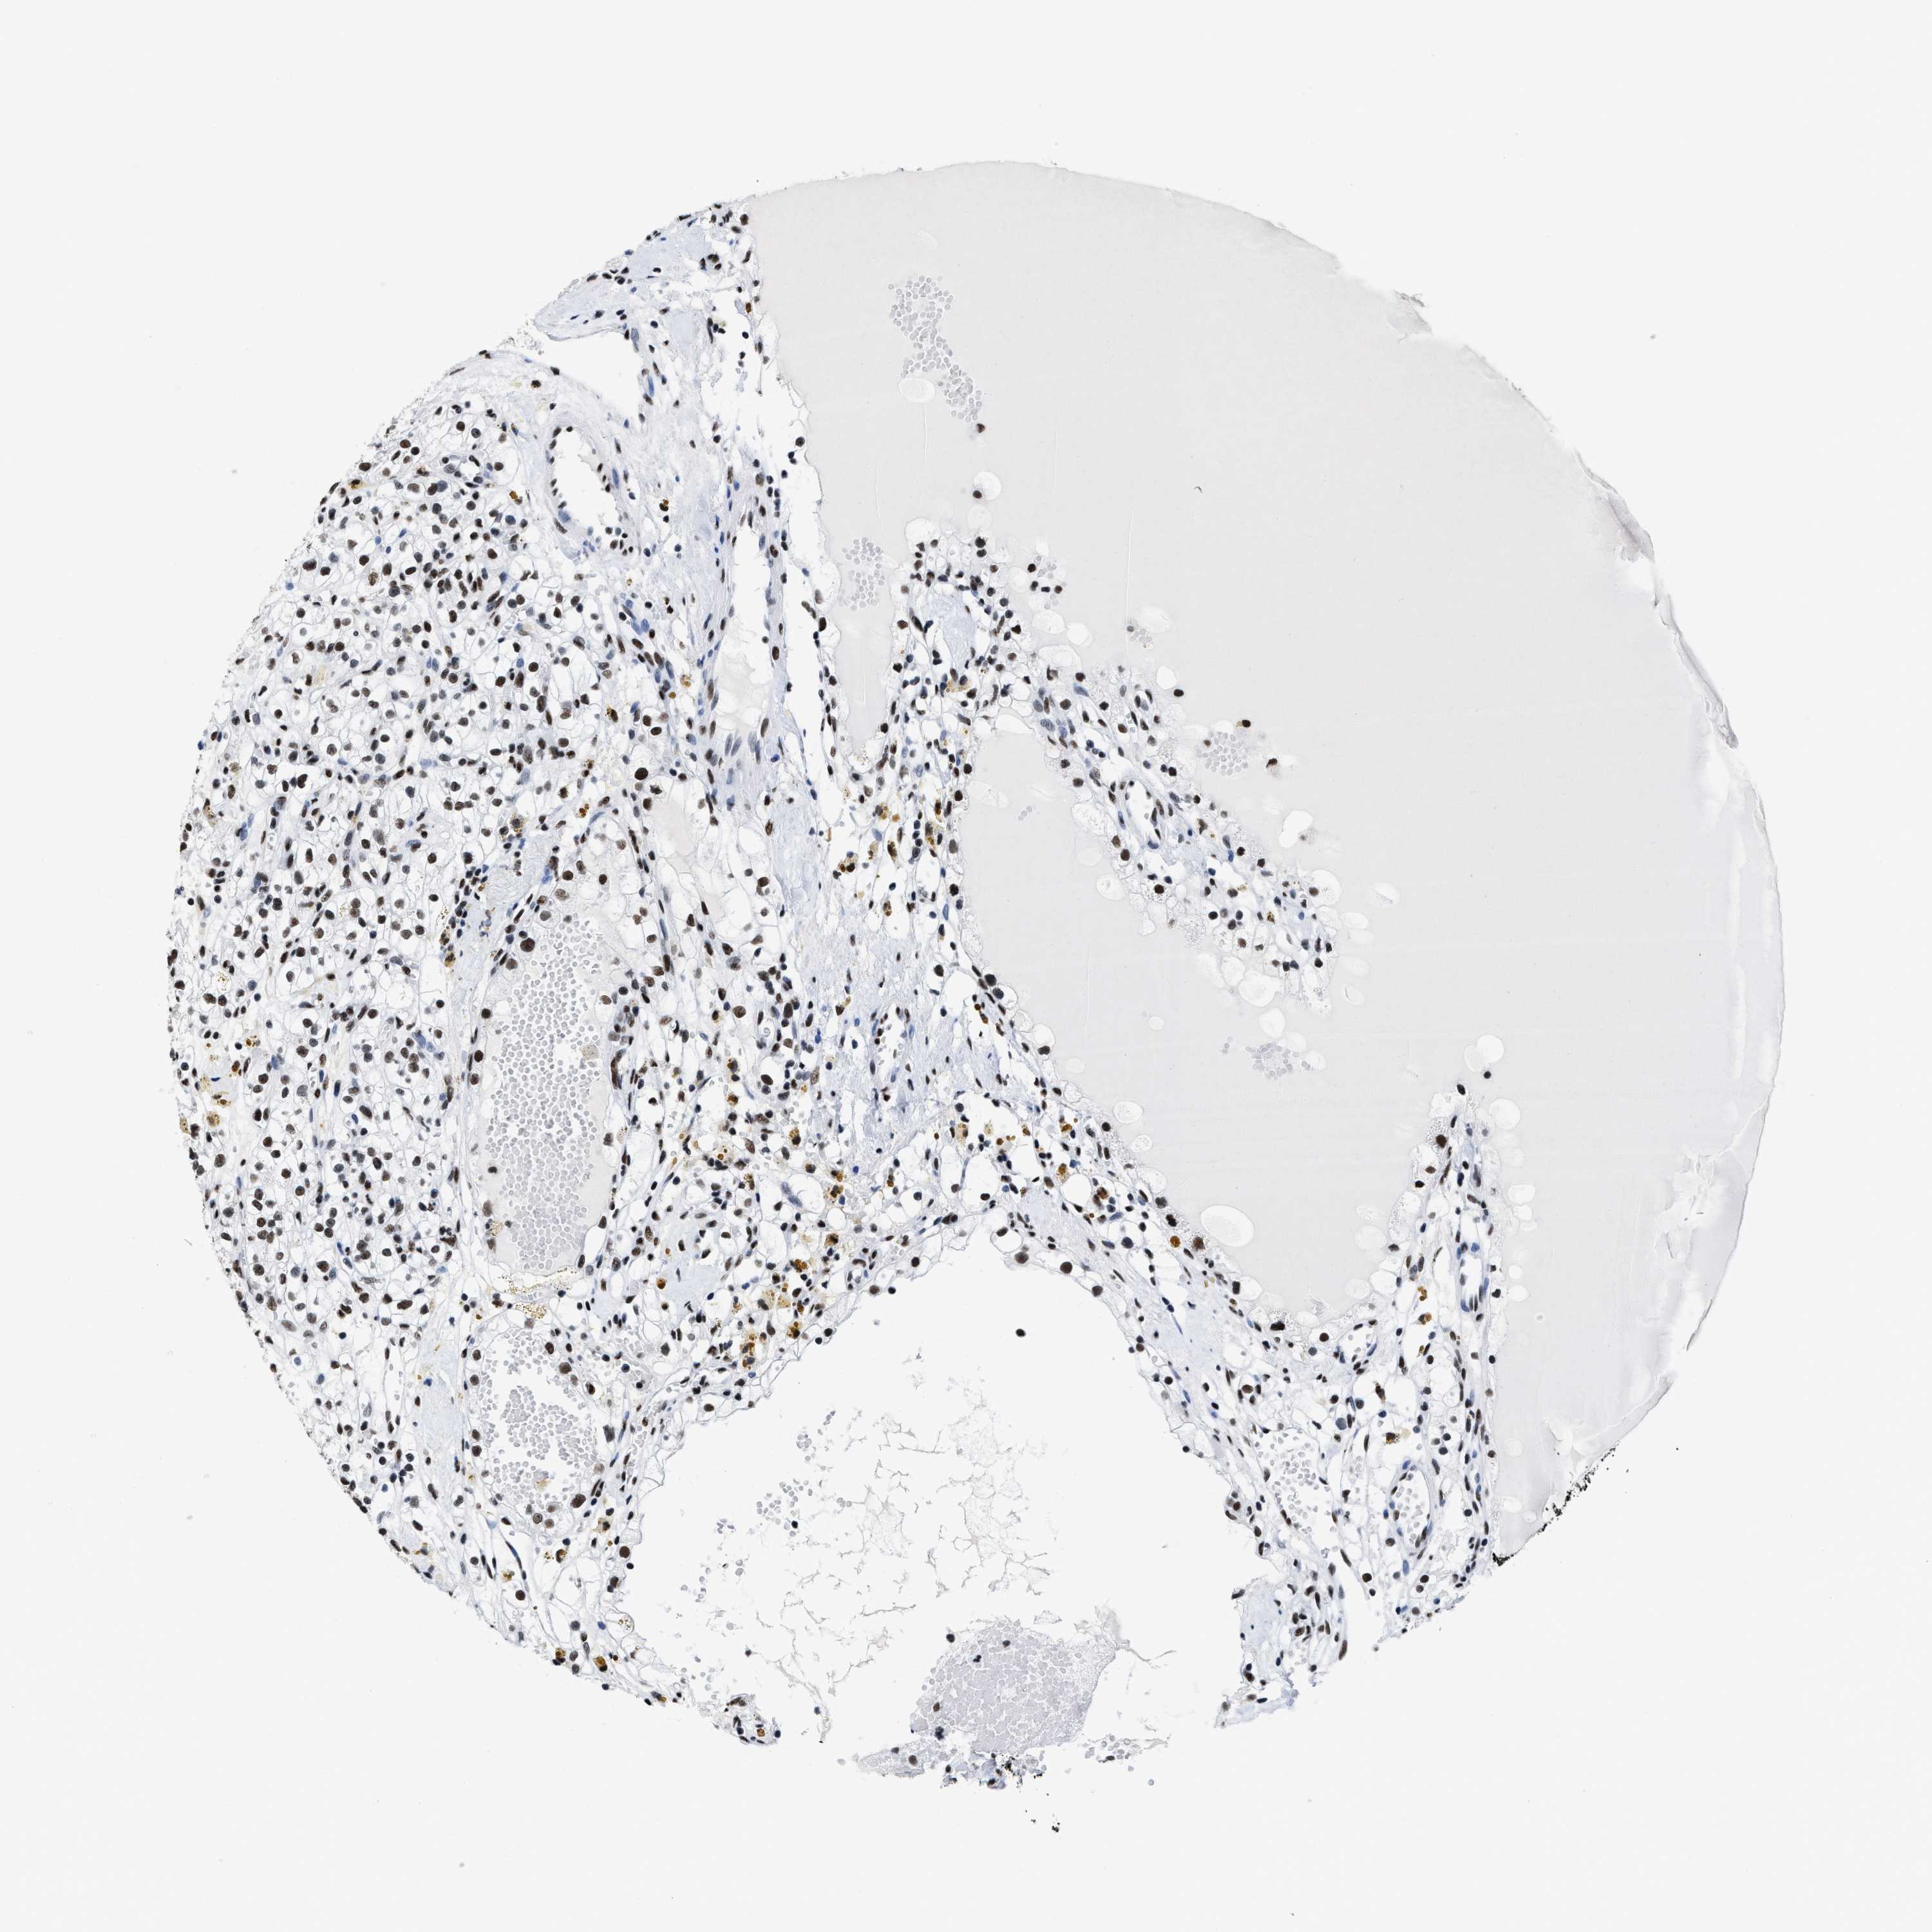

KIDNEY RENAL CLEAR CELL CARCINOMA (VALIDATION) - Interactive survival scatter ploti

The Survival Scatter plot shows the clinical status (i.e. dead or alive) for all individuals in the patient cohort, based on the same data that underlies the corresponding Kaplan-Meier plots. Patients that are alive at last time for follow-up are shown in blue and patients who have died during the study are shown in red.

The x-axis shows the expression levels (FPKM) of the investigated gene in the tumor tissue at the time of diagnosis. The y-axis shows the follow-up time after diagnosis (years). Both axes are complimented with kernel density curves demonstrating the data density over the axes. The top density plot shows the expression levels (FPKM) distribution among dead (red) and alive patients (blue). The right density plot shows the data density of the survived years of dead patients with high and low expression levels respectively, stratified using the cutoff indicated by the vertical dashed line through the Survival Scatter plot. This cutoff is automatically defined based on the FPKM cutoff that minimizes the p-score. The cutoff can be changed by dragging the vertical line or by entering a cutoff value in the square labeled "Current cut-off".

Under the Survival Scatter plot the p-score landscape (black curve; left axis) is shown together with dead median separation (red curve; right axis). Dead median separation is the difference in median mRNA expression between patients who have died with high and low expression, respectively. It is calculated as follows: median FPKM expression of dead patients with high expression - median FPKM expression of dead patients with low expression. This is intended to aid the user in visually exploring custom cutoffs and the associated p-scores and dead median separation.

Individual patient data is displayed and can be filtered by clicking on one or more of the category buttons on the top of the page. Categories describing expression level and patient information include: high, low, alive, dead, female, male and tumor stages. The scale of the x-axis can be toggled between linear and log-scale by clicking on the "x log" button. Mouse-over function shows TCGA ID, patient information and mRNA expression (FPKM) for each patient.

& Survival analysisi

Kaplan-Meier plots summarize results from analysis of correlation between mRNA expression level and patient survival. Patients were divided based on level of expression into one of the two groups "low" (under cut off) or "high" (over cut off). X-axis shows time for survival (years) and y-axis shows the probability of survival, where 1.0 corresponds to 100 percent.

SMARCC2 is not prognostic in Kidney Renal Clear Cell Carcinoma (validation)

Best expression cut offi

Based on the FPKM value of each gene, patients were classified into two groups and association between prognosis (survival) and gene expression (FPKM) was examined. The best expression cut-off refers the FPKM value that yields maximal difference with regard to survival between the two groups at the lowest log-rank P-value. Best expression cut-off was selected based on survival analysis .

When clicking on this number, the vertical dashed line indicating cut-off, the interactive survival plot, and the Kaplan-Meier curve will be adjusted to show results based on the best expression cut-off.

: 44.04

P scorei

Log-rank P value for Kaplan-Meier plot showing results from analysis of correlation between mRNA expression level and patient survival.

N/A

TCGA RNA samplesi

RNA-seq data is reported as average FPKM (number Fragments Per Kilobase of exon per Million reads), generated by the The Cancer Genome Atlas (TCGA) .

Normal distribution across the dataset is visualized with box plots, shown as median and 25th and 75th percentiles. Points are displayed as outliers if they are above or below 1.5 times the interquartile range. FPKM values of the individual samples are presented next to the box plot.

Average pTPM 43.8

Number of samples 100